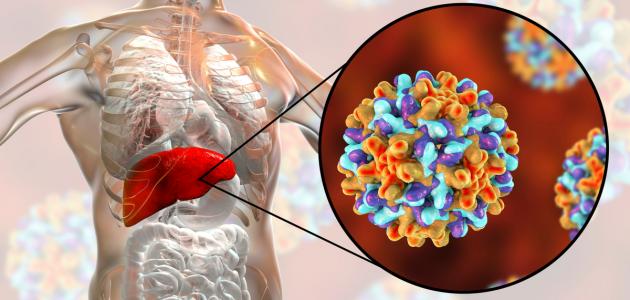

فيروس الكبد ب، أو التهاب الكبد الوبائي ب، أو التهاب الكبد الفيروسي ب، أو مرض الوباء الكبدي ب، أو مرض الكبد الوبائيّ ب (بالإنجليزية: Hepatitis B)، جميعُها مصطلحات تُشير إلى تضرر الكبد والتهابه الناجم عن الإصابة بعدوى فيروسية من نوع فيروس الكبد الوبائي “ب”، ومن الجدير ذكره أنّ هذه العدوى قد تكون حادّة أو مزمنة، وإنّ الالتهاب يتمثّل بانتفاخ أنسجة الجسم المُتأثرة بالإصابة أو العدوى، وقد يترتب على ذلك الإضرار بأعضاء جسم الإنسان، ومن الجدير ذكره أنّ الفيروسات قد تنتقل من شخصٍ لآخر بحيث تغزو خلايا الجسم الطبيعية، وحول طُرق انتقال فيروس الكبد الوبائي “ب” فإنّها تتمّ عن طريق الاتصال مع سوائل جسم مُصاب بهذا الفيروس؛ بما يتضمّن الدم أو السّائل المنوي أو أيّ سوائل أخرى، ويُمكن تحقيق الوقاية من خلال تجنّب العوامل التي من شأنها نقل العدوى إضافةً إلى تلقي المطاعيم الآمنة والفعّالة في الحماية من هذه العدوى، وتبعًا لإحصائيات منظمة الصحة العالمية (بالإنجليزية: World Health Organization) عام 2015م فإنّ المُصابين بالتهاب الكبد الوبائي “ب” المُزمن ممّن يُظهرون نتائجًا إيجابيّة لاختبار مولدات الضد السطحية لفيروس التهاب الكبد (ب) (بالإنجليزية: Hepatitis B Surface Antigen) واختصارًا (HBsAg) يبلغ عددهم حوالي 257 مليون مُصاب، ووفقًا لإحصائيّاتها عام 2016م فإنّ ما يُقارب 27 مليونًا من المُصابين بهذه العدوى يُدركون إصابتهم بها، في حين يبلغ عدد الخاضعين للعلاج 4.5 مليون مُصاب ممّن تمّ تشخيصهم بهذه الحالة.[١][٢]

كما تمّت الإشارة سابقًا فإنّ التهاب الكبد الوبائي “ب” يُعزى إلى العدوى بفيروس الكبد الوبائي “ب”، وقد تظهر بعض الأعراض على المُصابين بهذا المرض دون أن يُدرِكوا إصابتهم بهذه العدوى، وعليه فإنّه ذلك قد يتسبّب بنقل العدوى للآخرين دون معرفتهم بذلك، وإنّ عدم إجراء التدخلات الفورية والفعّالة قد يتسبّب بزيادة عدد المُصابين بالعدوى، وتنتشر هذه العدوى في بعض مناطق العالم وتكون شائعة في مناطق مُعينة أكثر من غيرها، ويُشار إلى اختلاف النمط الجيني للفيروس المُنتشر أيضًا من بلدٍ لآخر، إذ يُعتبر النمط الجيني “أ” لفيروس الكبد الوبائي “ب” هو الأكثر انتشارًا في الولايات المُتحدة الأمريكية، بينما يُعدّ النمط الجيني “د” هو السّائد في مناطق الشرق الأوسط ومعظم دول أوروبا، ويُمكن تصنيف المناطق الجغرافية بناءً على شدّة العدوى إلى شديدة العدوى أو متوسطة العدوى،[٤] [٥] وفيما يأتي بيان لأبرز مناطق العالم التي تنتشر فيها العدوى بهذا الفيروس:[٦]